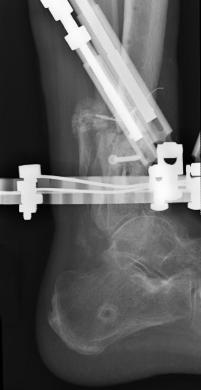

Postoperative (13th) images of left ankle

The image(s) displayed here were created following Liam's 13th surgery which was performed by Dr. Saunders. After a few hiccups getting

the surgery scheduled, Liam spent most of the September 13th afternoon in his 13th surgery. ;-) The surgery lasted about 5 hours and according

to the doctor, it was a good surgery. The 1st photo shows the new frame bracing that holds Liam's ankle together. The next series of photos show

various angles of the ankle and the rods that go from the frame into and through the left ankle. There was some concern that the swelling would

burst and allow for infection. Looks like we are now past that concern. Liam is still on antibiotics to ward of potential infection. The flesh

images show how the skin reacts to having the leg adjusted by the brace. The doctor has had to cut the skin to allow the rods to move freely.